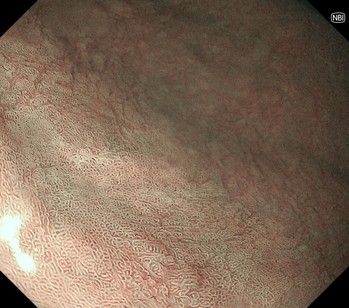

➂NBI併用拡大観察

陥凹内に腫瘍血管を認め、腫瘍性病変と診断 病理診断: 4mm Group3 (胃腺腫)

④NBI併用拡大観察

病変内は異型血管を認めず、窩間部の開大所見あり